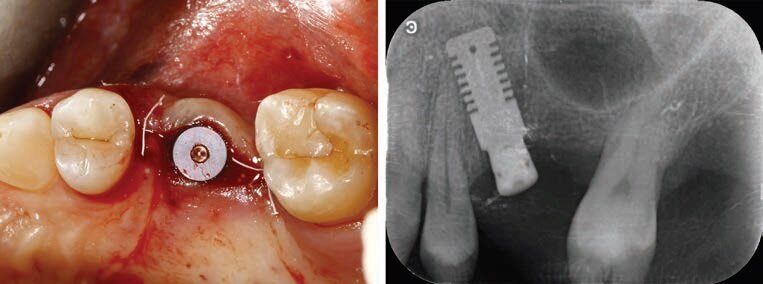

Si procede quindi con l’inserimento dell’impianto, che essendo press-fit, sarà effettuato con il percussore magnetico IPD. Normalmente un corretto posizionamento dell’impianto richiede 10/12 spinte a potenza crescente. Dopo l’inserimento dell’impianto alla corretta profondità, verrà posizionata la vite di copertura (Fig. 6) in attesa della guarigione e dell’osteointegrazione dell’impianto. A 6 mesi dall’inserimento, verrà rimossa la vite di copertura e avvitato il moncone Ti-Base sull’impianto, sul quale applicheremo a incastro il transfer digitale REX marker che sarà rilevato dallo scanner intraorale oppure da uno scanner da banco qualora venga fatta dall’odontotecnico la scansione sul modello in gesso. In alternativa potremmo avvitare lo specifico REXmarker direttamente sull’impianto REX PiezoImplant (Fig. 7).

Fig. 6 - Fine chirurgia.

Fig. 7 - Ti Base, Scanmarker per Ti Base, Scanmarker per fixture.